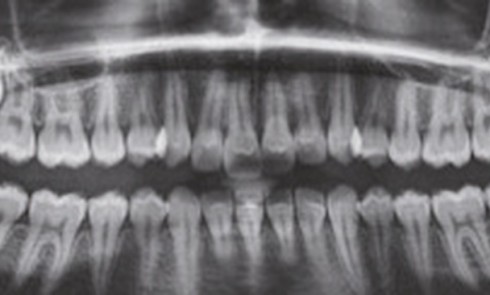

Présentation du cas (fig. 1 à 9) Madame J, âgée de 49 ans, nous est adressée par son occlusodontiste pour...